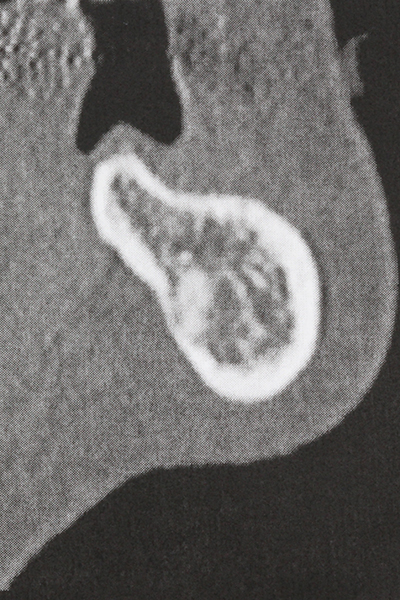

Die Präparation des lateralen Fensters bei der externen Sinusbodenelevation stellt gerade für chirurgisch unerfahrene Implantologen eine große Herausforderung dar. Die knöcherne Bedeckung der Kieferhöhle ohne eine Verletzung der darunterliegenden Schneider’schen Membran abzutragen ist dabei nur ein Teil der Operation – nach Schaffung eines ausreichenden Zugangs muss die Kieferhöhlenschleimhaut vorsichtig mobilisiert werden, um Raum für das einzubringende Material bzw. die Implantate zu schaffen. In dieser Indikation ist die Piezochirurgie zweierlei hilfreich: zum einen kann durch Verwendung diamantierter Instrumente eine selektive Knochenabtragung erfolgen und die darunter liegende Schleimhaut bleibt bei vorsichtiger Vorgehensweise intakt. Zum anderen unterstützen die Ultraschallfrequenzen zusätzlich eine komplikationslose Ablösung der Schleimhaut – sie werden durch spezielle stumpfe Ansätze in den Spaltraum zwischen Schleimhaut und Kieferhöhlenboden übertragen (Cassetta, Ricci et al. 2012, Pereira, Gealh et al. 2014) (Rickert, Vissink et al. 2013). So erscheint es nicht verwunderlich, dass in aktuellen Übersichtsarbeiten über die externe Sinusbodenelevation neben der Verwendung von rauen Implantatoberflächen und dem Einsatz von Knochenersatzmaterialien auch der Einsatz von piezoelektronischen Geräten als positiv bewertet wird (Wallace, Tarnow et al. 2012).